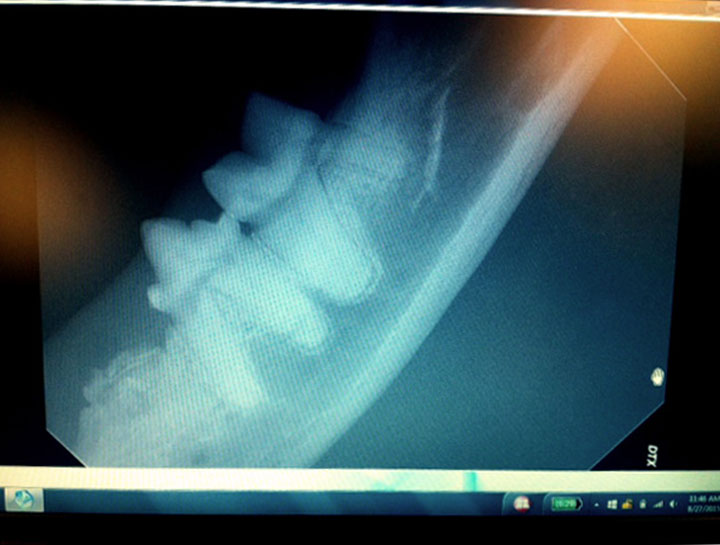

Pet Digital Radiology

Digital x-rays assist in diagnosing illness & injury.